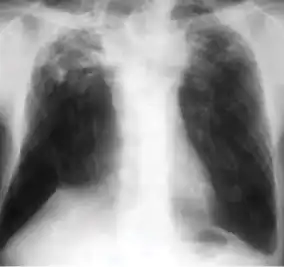

Chest x-ray of Ghon's complex of active tuberculosis